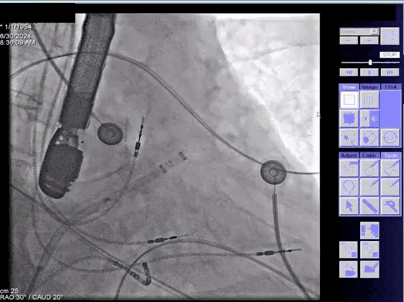

▲测量心耳直径

在工作体位下测得锚定区:21mm、封堵区:19mm,选用 LAxible™ 2632常规型号的封堵器。